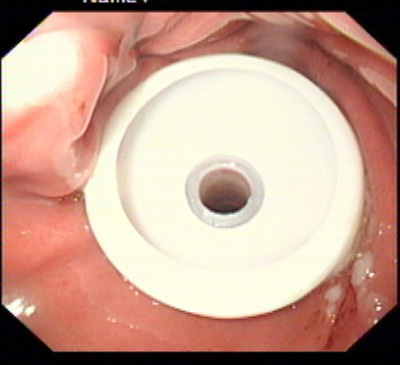

在消化科董蕾主任关心和指导下,消化科王进海教授,张利医师成功地给一位脑出血后吞咽困难的患者实施了经皮内镜下胃造瘘术。

该患者系男性,76岁,脑出血后留有吞咽困难后遗症,不能自主进食,需长期留置胃管供给营养,严重的影响了病人的生活质量和原发病的恢复。经皮内镜下胃造瘘术(Percutaneous endoscpic gastrostomy,PEG)是一种无需常规外科手术和全身麻醉的造瘘技术,可以在胃镜室或病房局麻下进行,因此是一种操作简便、创伤小、安全可靠的方法。该例患者在胃镜室局麻下进行手术,手术过程约10分钟,术后病人无明显不适,3天后即可从造瘘管给食物并出院。

该手术的成功填补了院内空白,丰富了内镜下治疗的内容。对于各种原因造成的长期或较长期不能(一月以上)经口进食者,可通过造瘘管供给病人足够的营养物质,效果优于传统的鼻胃管饲营养,费用又明显低于静脉内营养,是一项值得推广的内镜下较为安全的治疗技术。经皮内镜下胃造瘘术适应证包括:①中枢神经系统或全身性疾病导致的吞咽困难或不能吞咽。如:脑干炎症、变性,脑血管意外,脑肿瘤, 脑外伤;急性呼吸衰竭;系统性硬化症、重症肌无力;完全不能进食的神经性厌食或神经性呕吐导致严重的营养不良,而不能耐受手术造瘘者;②口、咽、喉手术前后及头颈部肿瘤放疗期间,需较长时间营养支持者。③食管广泛瘢痕者;④严重的胆外瘘需将胆汁引回胃肠道者;⑤各种原因所致呼吸功能障碍须气管切开,同时需PEG者;⑥胃肠减压(一月以上的鼻胃管留置者)的目的。